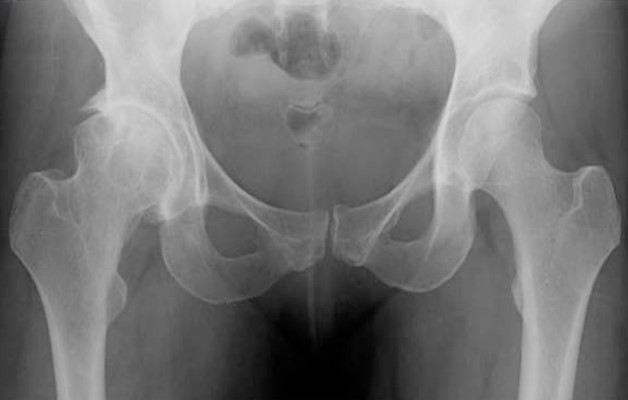

- Незначительное сужение суставной щели и начало образования краевых остеофитов заметны на 1 степени заболевания. При этом незначительный дискомфорт возникает только при длительных нагрузках на сустав. Во время отдыха неприятные ощущения пропадают.

- На 2 степени коксартроза остеофиты ярко выражены, суставная щель значительно сужена, может наблюдаться подвывих бедренной кости. Человек ощущает боли, которые возникают даже при недолгой нагрузке. Амплитуда движений ограничивается, мышечная сила бедра снижается.

- На 3 степени заболевания суставная щель не просматривается, головка бедра и вертлужная впадина теряют форму, сустав приобретает неестественное положение. Боли носят постоянный характер. Суставы выглядят опухшими, конечность укорачивается. Если коксартроз затрагивает оба сочленения, человек не может передвигаться без помощи специальных приспособлений (костылей, ходунков).

Диагноз диспластический коксартроз ставится на основании жалоб пациента и инструментальных исследований. Чаще всего назначают рентгенографию, которая позволяет установить степень патологии. Если возникают спорные вопросы, врач может дополнительно назначить проведение компьютерной (КТ) или магнитно-резонансной томографии (МРТ). КТ позволяет более детально увидеть состояние костных структур, а МРТ оценить нарушения в мягких тканях и кровеносных сосудов. Иногда пациента направляют на биохимический анализ крови, чтобы исключить другие патологии и воспаления.